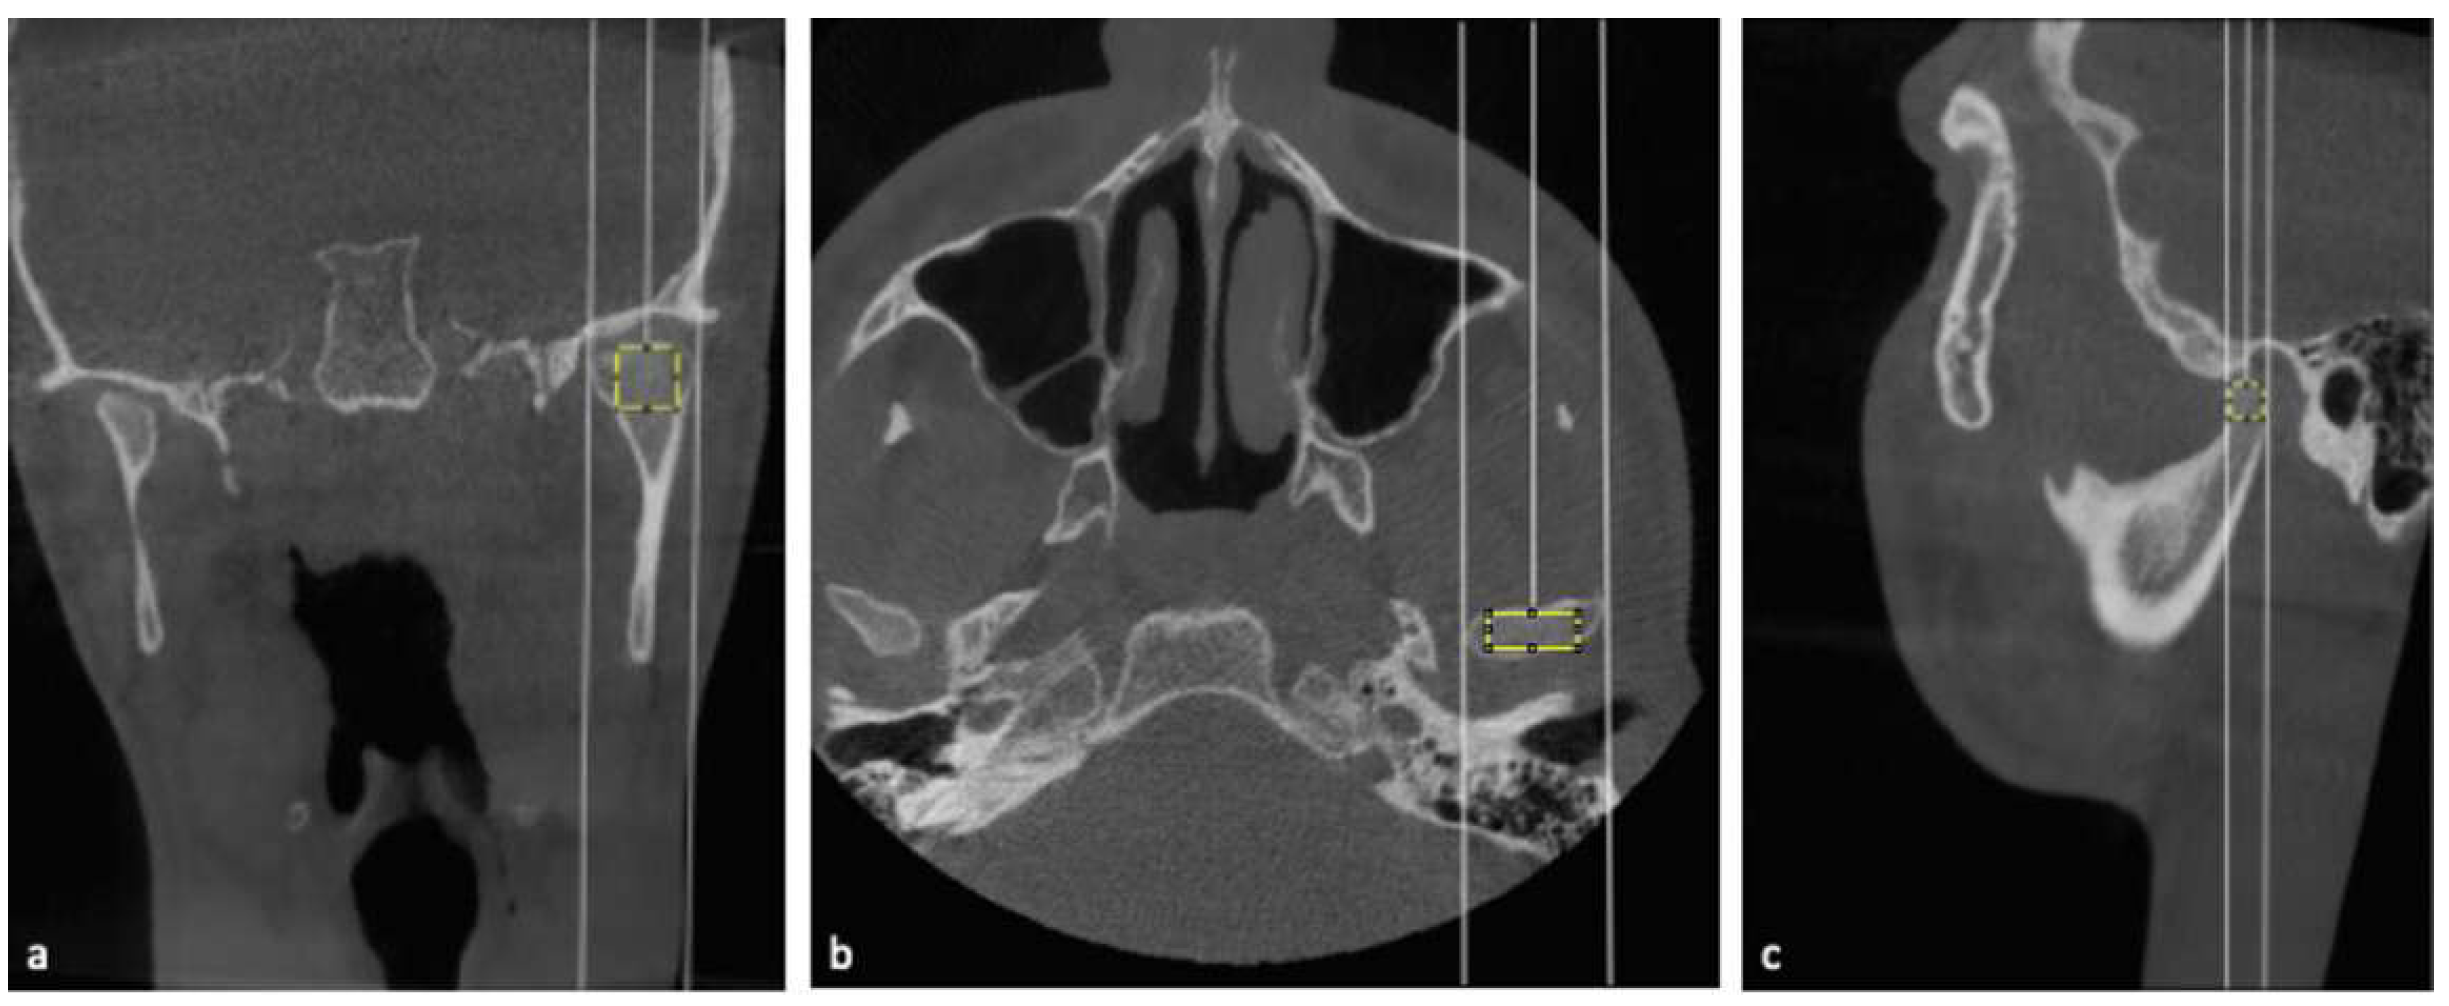

2.2. Fractal Dimension Analysis